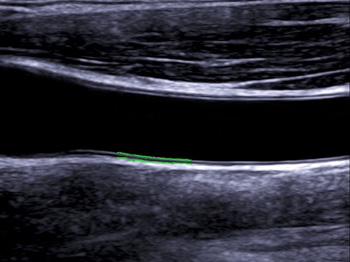

- Авто расчет толщины комплекса интима-медиа (IMT)

Автоматический расчёт комплекса интима-медиа. Данная функция призвана облегчить вашу работу, исключая человеческий фактор из проведения тонких расчетов во время исследования комплекса интима-медиа, тем самым радикально снижая риски допущения врачебной оши